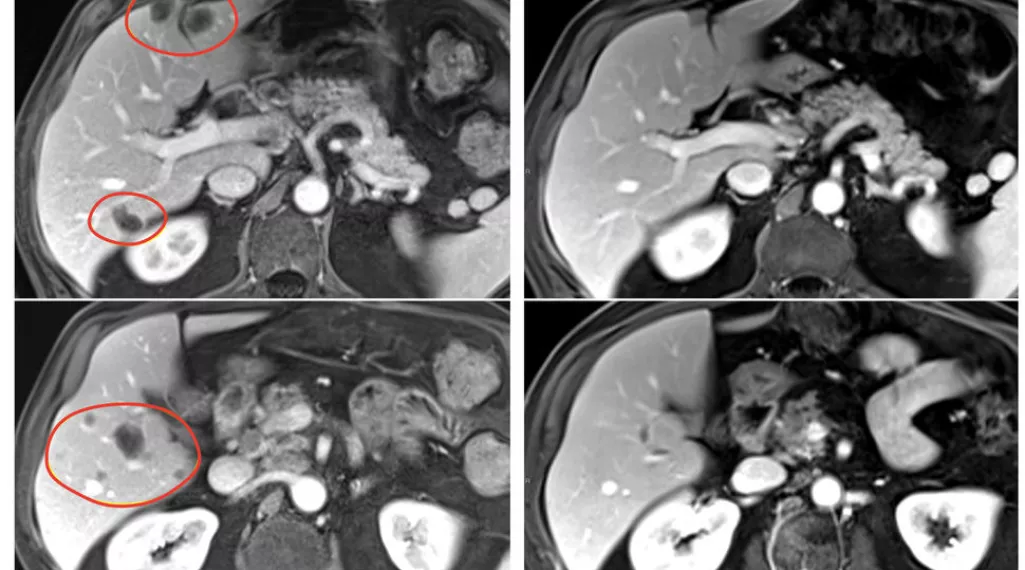

Patients in the clinical trial, who had a variety of gastrointestinal tumors, also received the immune checkpoint inhibitor pembrolizumab (Keytruda) to help further boost their immune response. The result was nearly 24% of patients treated with selected TILs plus pembrolizumab had a substantial reduction in the size of their tumors, compared with 7.7% of patients who received selected TILs without pembrolizumab. Patients treated with TILs that had not been selected for anti-tumor activity had no tumor shrinkage.

In the third phase, 34 patients received pembrolizumab immediately before selected TIL therapy to prevent the newly introduced immune cells from becoming inactivated by the patient’s own immune system. This group had the best response, with 8 of 34 (23.5%) patients experiencing an objective response. All 91 patients had also received standard chemotherapy and high-dose interleukin-2 before the TIL therapy.